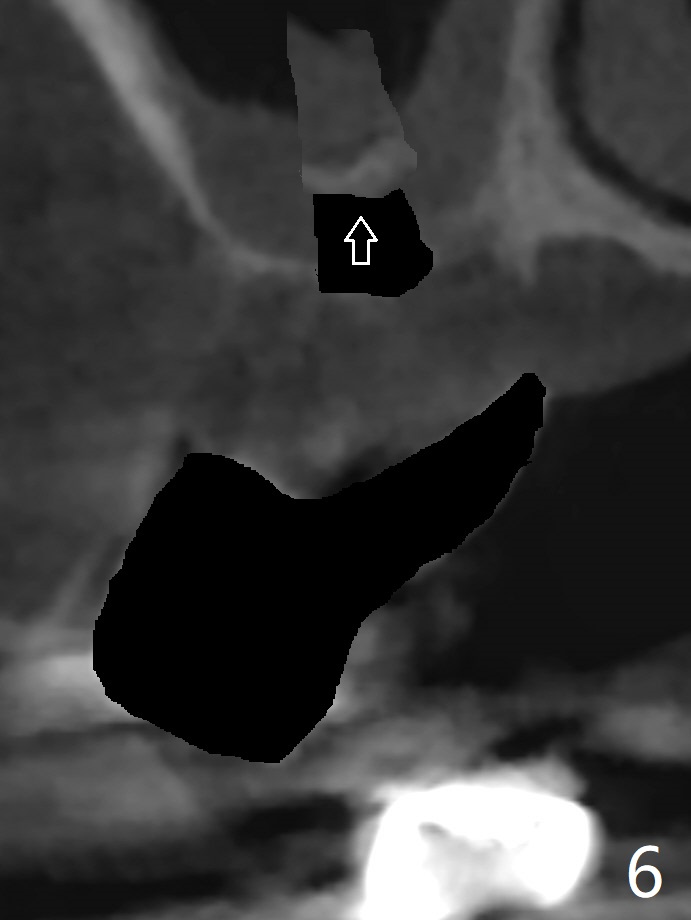

A 51-year-old woman has poor dentition with chronic periodontitis (Fig.1). She has financial constraint, but refuses RPD, insisting upon UR posterior implants first. After discussion of severe bone loss, she agrees with bone graft first (Fig.2-4). Since the bone atrophy is the most severe at #3 (Fig.5 coronal section; L: lingual), sinus lift (Fig.6 arrow) is conducted after extraction (black). Use sticky bone (Fig.7 red circles) and Titanium-reinforced Cytoplast (white) for socket preservation. Or if Magicore is able to achieve primary stability (Fig.8 green), an abutment (pink) will be placed for an immediate provisional (white). The latter are capable of holding bone graft in place. Since bone loss at #2 and 4 is less severe (Fig.9 sagittal section), their roots will act as walls to keep bone graft (Fig.11) in place after #3 extraction (Fig.10).